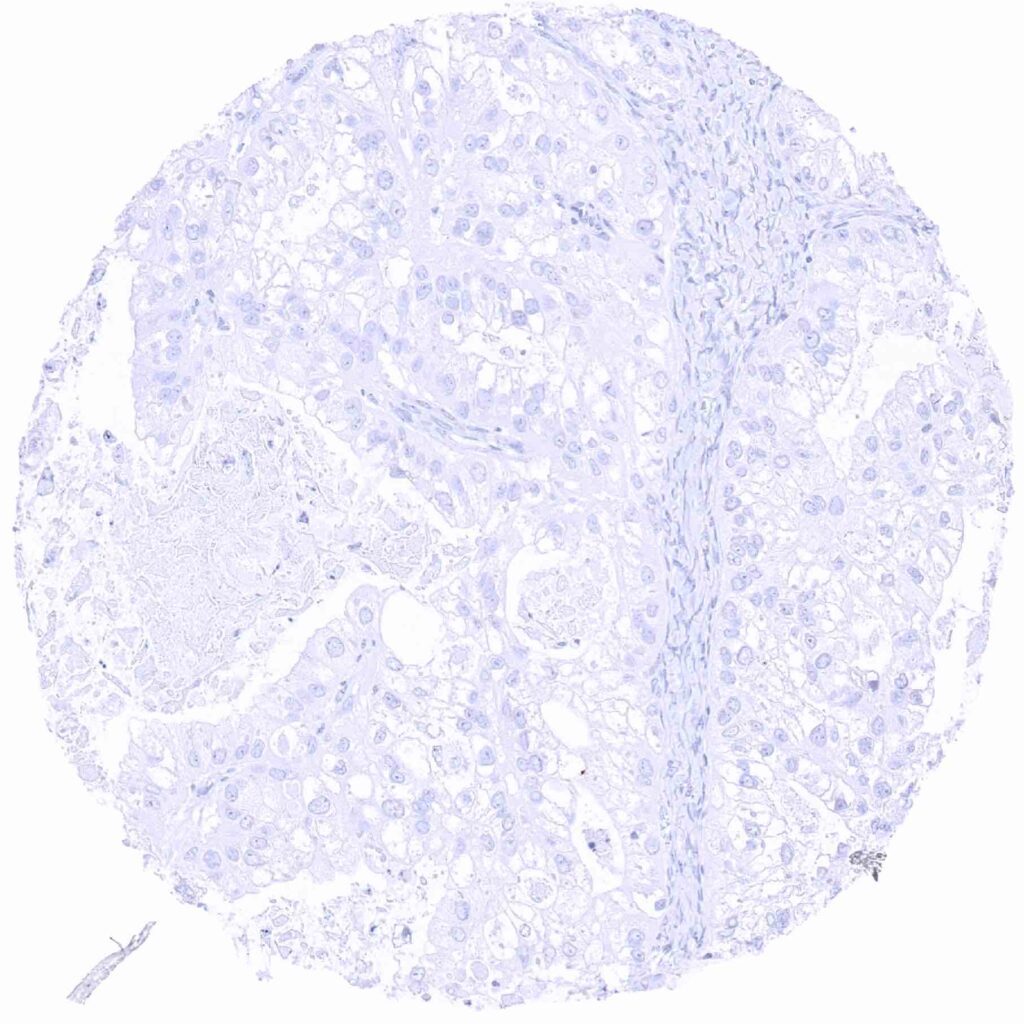

Ovary – Prostein negative clear cell carcinoma